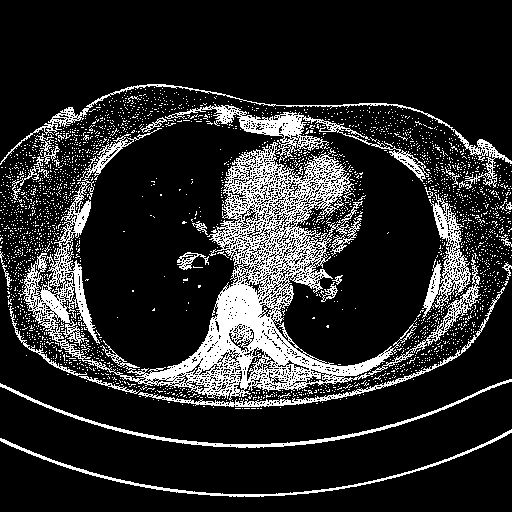

Original NATIVE CT scan (input)

Full window (WL 1023.5, WW 4095 β†’ Low βˆ’1024, High +3071)

Actual HU range: [-1024.0, 3071.0]